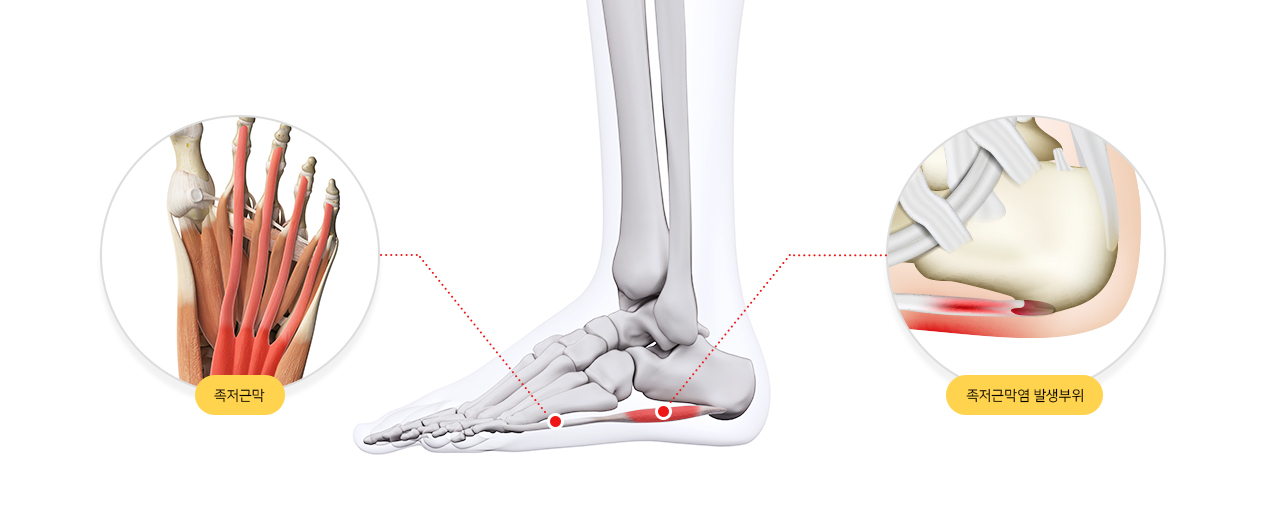

족저근막염이란?

발 뒤꿈치에서부터 발바닥 앞쪽까지의 발바닥 근육을 감싸고 있는 두꺼운 근막이 "족저근막"이라고 합니다. 족저근막이 발바닥의 아치를 유지하고, 걸을 때 스프링처럼 완충 작용을 하여 발을 보호해 주는 기능을 하는데, 이 족저 근막에 반복적인 미세 손상을 입어 염증이 발생한 것을 "족저근막염"이라고 합니다. 대게 40~50대의 여성에게 많이 발생합니다.